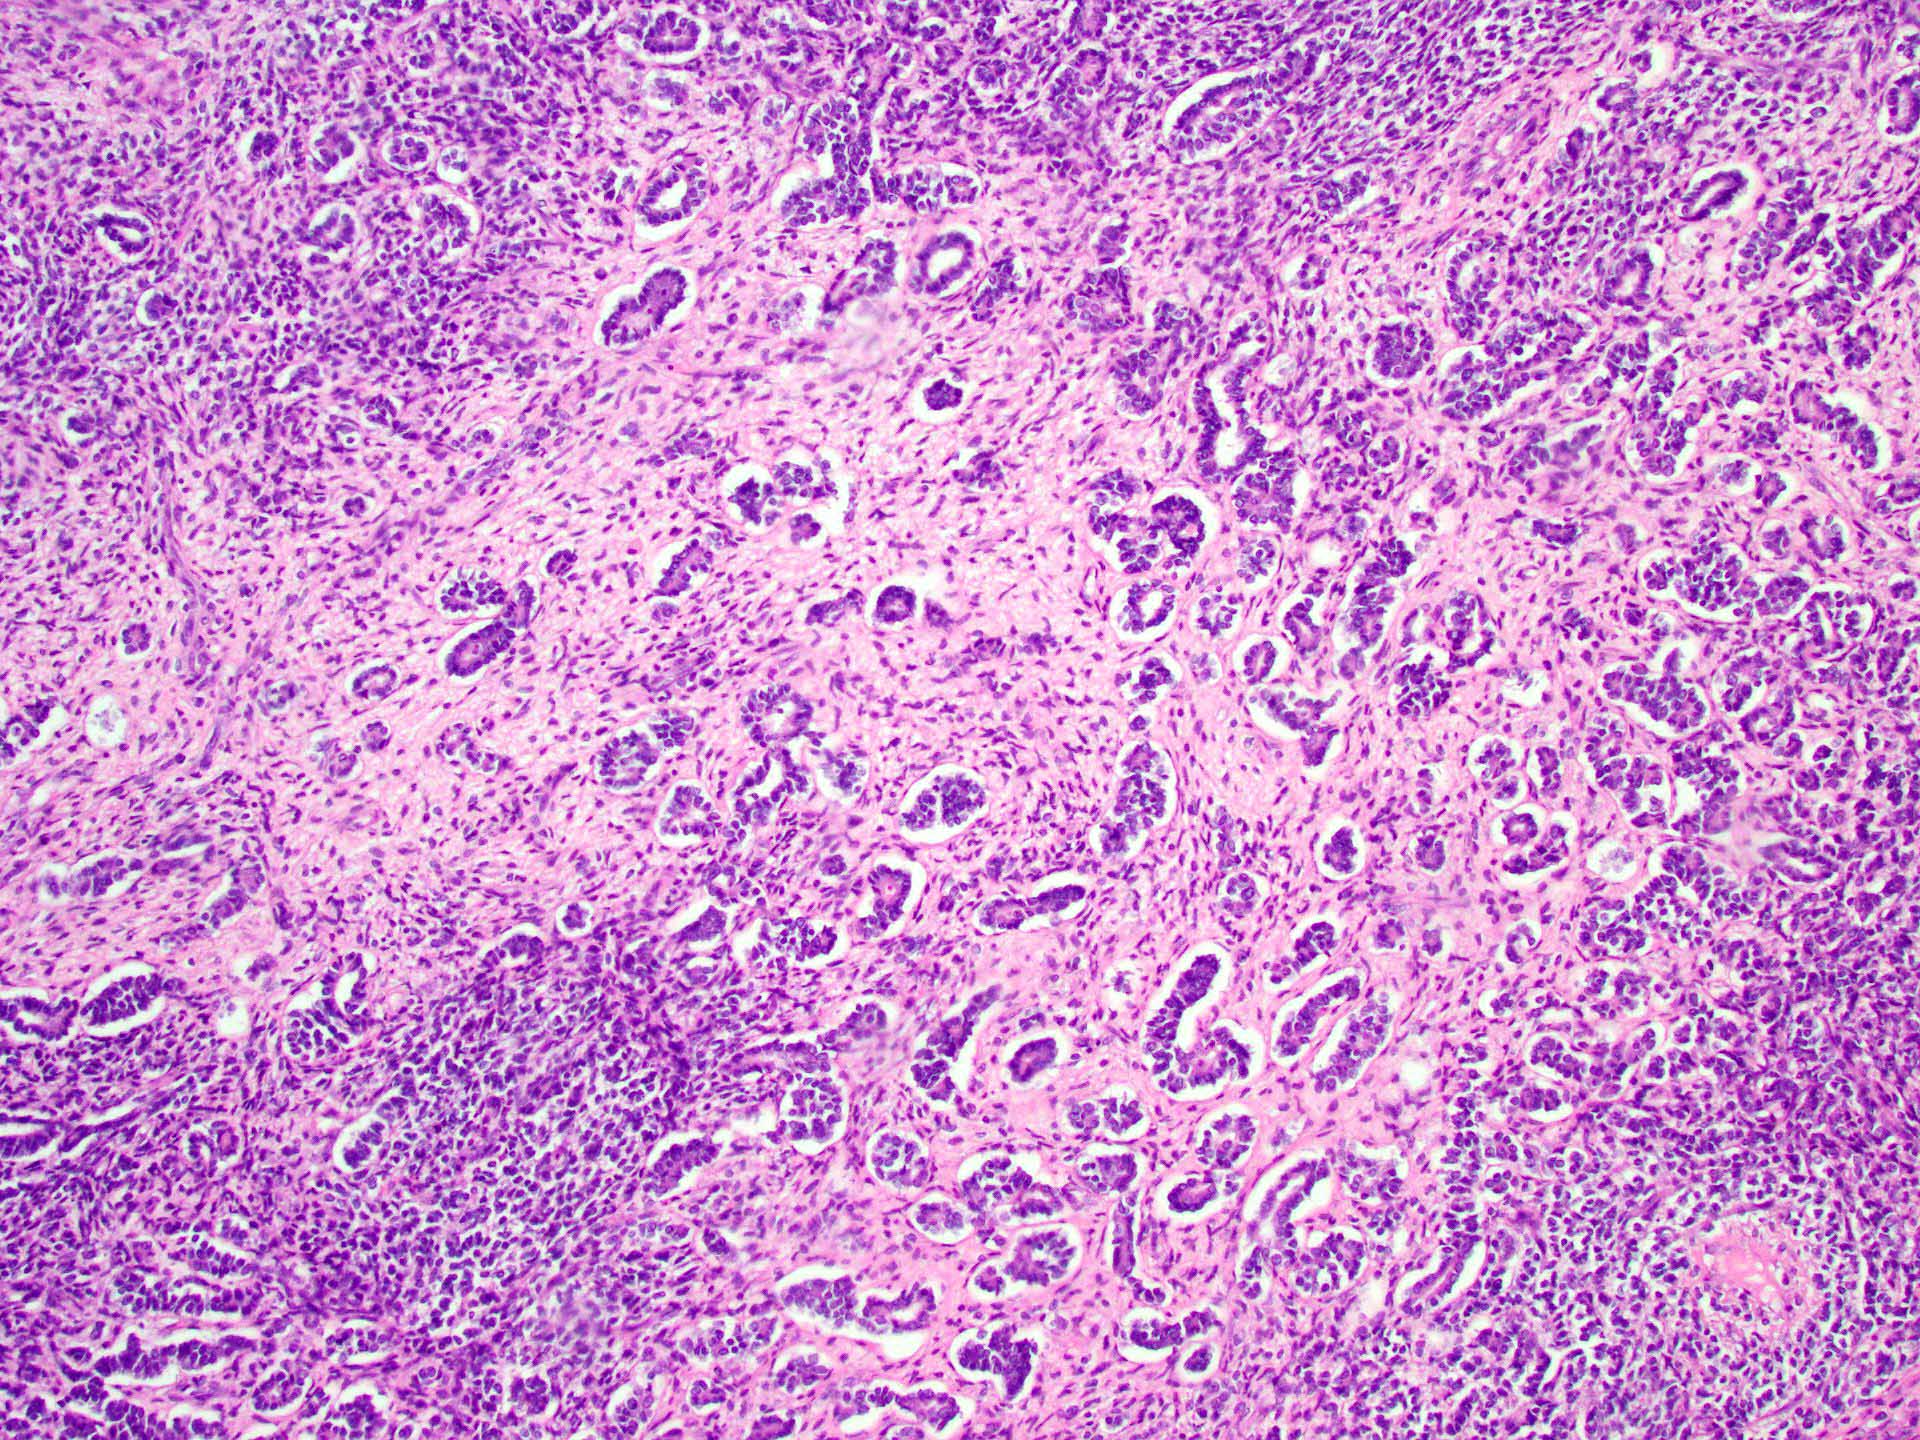

Microscopic (histologic) description

- Tubular pattern (most common and usually present at least focally) with solid or hollow tubules

- Cuboidal or columnar cells

- Bland oval to round, monotonous nuclei

- Pale cytoplasm

- Lipid rich or oxyphilic variants may be associated with Peutz-Jeghers syndrome

- Other patterns: trabecular, diffuse, alveolar, pseudopapillary, reniform, pseudoendometrioid, spindled

- Absent to very rare Leydig cells

- Pathologic features predictive of malignant behavior include 5 mitoses per 10 high power fields, severe cytologic atypia, necrosis and size > 5 cm

A 40 year old woman is seen in the clinic with complaints of irregular uterine bleeding and pelvic fullness. Transvaginal ultrasound shows a 9 cm right ovarian mass. The mass is surgically removed and a pathologic examination shows the features in the picture above. The mass is positive for inhibin and SF1. The tumor is negative for EMA, PAX8, MelanA and chromogranin. In which of the following general categories does this tumor belong?

C. Pure sex cord tumor. Sertoli cell tumor is a pure sex cord neoplasm of the ovary composed of Sertoli cells most commonly arranged in a tubular pattern. Sertoli cells are positive for inhibin and SF1. Answer D is incorrect because no Leydig cells, which are positive for MelanA and are stromal in nature, are present. Answer B is incorrect because the tumor is negative for neuroendocrine markers. Answer A is incorrect because the tumor is negative for EMA and PAX8.